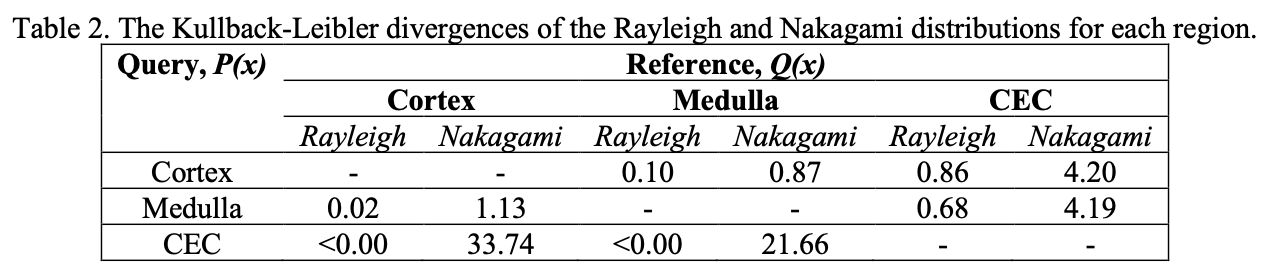

Kullback-Leibler Divergences and Goodness of Fit

After identifying the distributions with parameters that were significantly different between all three kidney regions, we evaluate the goodness of fit and relative entropy. To evaluate the quality of the estimated distributions to the underlying data, the goodness of fit is used. This is defined the sum of squares error across all images and masks for each of the distributions. To identify which of the distributions best separates the three regions, the Kullback-Leibler divergence (relative entropy) is computed. Given on the domain of , the Kullback-Leibler divergence is a measure of the difference from a query probability distribution with respect to a reference probability distribution . Maximizing the divergence of probability distributions between regions may yield better characterization, as it avoids potential redundancies. Conceptually, the Kullback-Leibler divergence represents new information gained from another distribution which increases if the distributions are different. As the Kullback-Leibler divergence is asymmetric, all pairs are compared. Only distributions with parameters that have a statistically significant difference between each region are used.

Table 1 summarizes the parameters and if they were significantly different between regions. Only two distributions, Nakagami and Rayleigh, had parameters that achieved significant differences in all three regions. These two distributions were the only ones used for subsequent KL divergence and goodness of fit analysis. Table 2 summarizes the divergence values.

Given the higher divergence values, the Nakagami distribution captures the distinctiveness of each region in a compelling manner. In comparing the cortex and medulla for example, two regions which are visually close together in echogenicity and difficult to segment, the Nakagami distribution has higher divergences compared to the Rayleigh distribution. Table 3 summarizes the goodness of fit for these distributions.

We observe low fitting error in both distributions, with no significant differences in the sum of squares error for either one. While both Rayleigh and Nakagami distributions have excellent model fitting and divergence values, the Nakagami can be used in a more general manner than the Rayleigh. The Nakagami shape parameter, m, can be used to determined pre-Rayleigh, Rayleigh, and post-Rayleigh scattering conditions. We select this distribution for stratification.